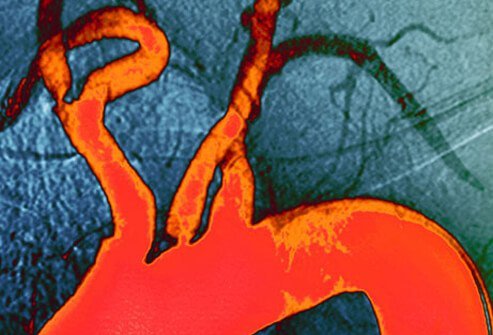

Cholesterol Level Health Screening

Cardiovascular Disease Link

Cholesterol is a fatty molecule that is present in the blood. Some amount is necessary to maintain health, but levels that are too high increase the potential for hardening of the arteries (atherosclerosis). Excess blood lipids can clog blood vessels in the arteries, leading to an eventual heart attack or stroke. Along with increased body mass index, smoking, diabetes, and other factors, high blood lipids are associated with the development of cardiovascular disease (CVD). Blood lipid panels should be a part of every woman's wellness health screenings.

Measuring Cholesterol Levels

Fasting Lipoprotein Panel

Most women should have their fasting cholesterol levels checked every 4 to 6 years beginning at age 20. This test measures the total cholesterol, HDL or "good," and LDL or "bad" levels of the blood lipids. A doctor may recommend a woman be screened more frequently if risk factors for cardiovascular disease are present. Lifestyle modifications including diet and exercise changes are effective for reducing high blood lipid levels. Medication is an option that works as well.